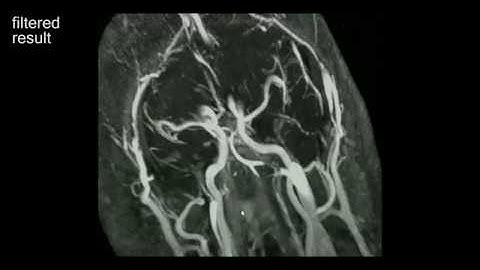

Data Assimilation for Full 4D PC‐MRI Measurements: Physics‐Based Denoising and Interpolation